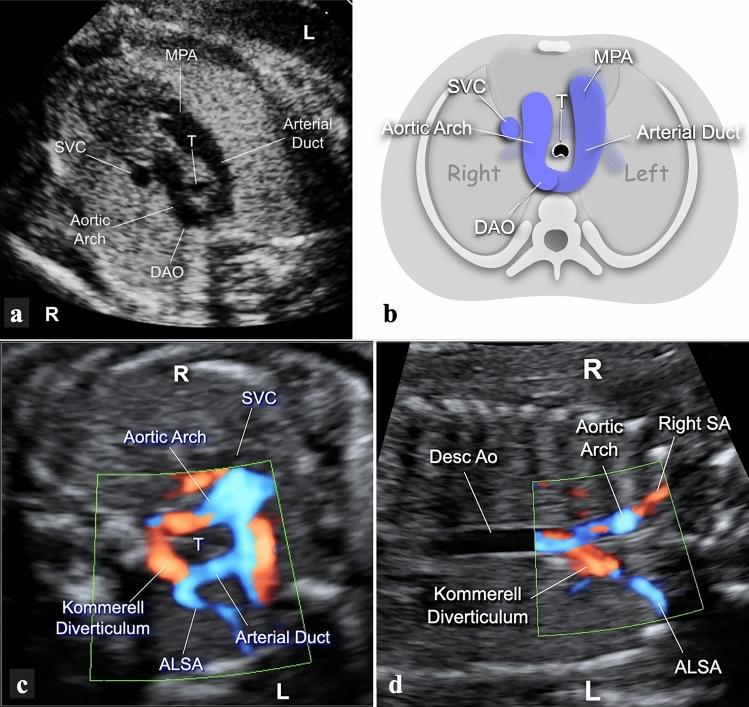

To study the different characteristics of arterial duct (AD) in a series of prenatally detected right aortic arch (RAA). Out of 832 congenital heart diseases (CHD) referred to a tertiary center, 98 cases had RAA. Based on anatomical landmarks we identified 7 types of AD: type 1 left-sided, transverse; type 2 left-sided, vertical; type 3 from the underside of aortic arch (AA), vertical; type 4 right-sided, mirror-image "V", transverse; type 5 right-sided, "H" shaped, transverse; type 6 bilateral; type 7 absent or unidentifiable. For each type of AD the incidence of associated major CHD was calculated and chi-square test was applied to verify the null hypothesis with significance level of p < 0.05. Type 1 occurred in 43% of cases including 4 with CHD and no cases with pulmonary outflow obstruction (POO). Symptoms of vascular ring were present in 41% of survivors. Type 2, 3 and 7 AD were associated with tetralogy of Fallot (TOF) or equivalents. No type 5 AD with CHD had POO and 3 isolated cases had asymptomatic hypoplasia of left pulmonary artery (LPA). Two type 6 AD had disconnection of LPA. Type 1 occurred more often as an isolated finding (p < 0.001), whereas types 2 (p = 0.0026), 3 (p = 0.0045), 4 (p = 0.0325) and 7 (p = 0.0001) were frequently associated with major CHD. In RAA, type 1 (U-shaped) is usually an isolated finding (p < 0.001) which includes all symptomatic vascular rings. POO is always present when the AD is vertical or absent but not when it lies on a transverse plane. Bilateral AD is rare and brings the risk of functionary loss of left lung if not identified.

研究一系列产前检测到的右主动脉弓(RAA)中动脉导管(AD)的不同特征。在转诊至三级中心的 832 例先天性心脏病(CHD)中,有 98 例存在 RAA。根据解剖学标志,我们确定了 7 种类型的 AD:1 型为左侧、横向;2 型为左侧、垂直;3 型为主动脉弓(AA)底部、垂直;4 型为右侧、镜像“V”形、横向;5 型为右侧、“H”形、横向;6 型为双侧;7 型为缺失或无法识别。对于每种类型的 AD,计算了相关主要 CHD 的发生率,并应用卡方检验来验证具有统计学意义的 p<0.05 的零假设。1 型发生在 43%的病例中,包括 4 例 CHD 患者和无肺流出道梗阻(POO)的患者。41%的幸存者存在血管环症状。2、3 和 7 型 AD 与法洛四联症(TOF)或等效物相关。无 CHD 的 5 型 AD 伴有 POO,3 例孤立性左肺动脉(LPA)发育不全。2 例 6 型 AD 存在 LPA 分离。1 型更常作为孤立性发现(p<0.001),而 2 型(p=0.0026)、3 型(p=0.0045)、4 型(p=0.0325)和 7 型(p=0.0001)常与主要 CHD 相关。在 RAA 中,1 型(U 形)通常为孤立性发现(p<0.001),包括所有有症状的血管环。当 AD 垂直或缺失时,POO 总是存在,但当 AD 位于横平面时则不存在。双侧 AD 罕见,如果未识别,会导致左肺功能丧失。